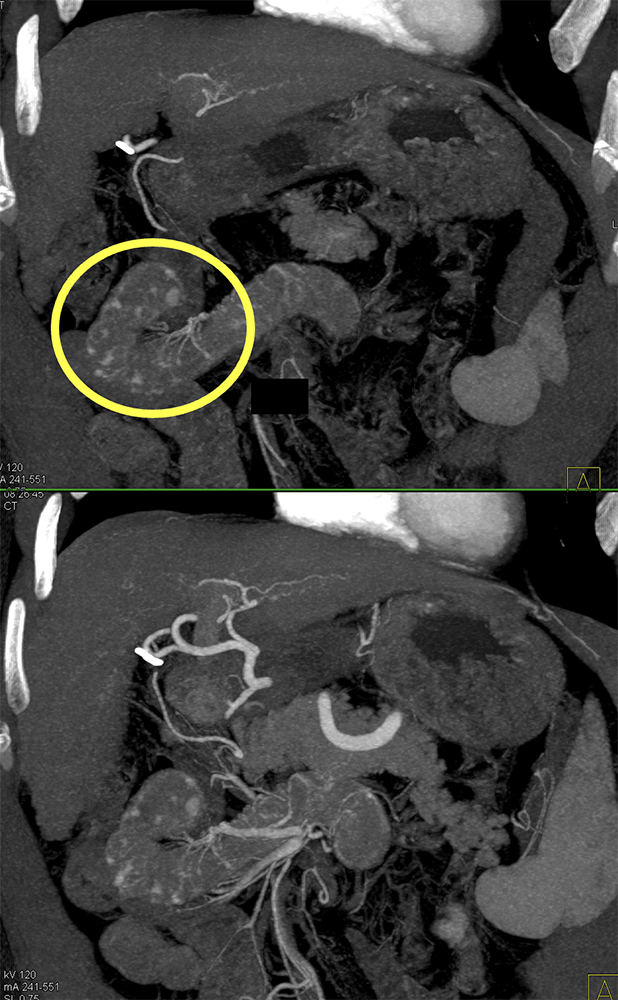

GIST Tumor Jejunum as the Cause of GI Bleeding ![]() |

![]() |

GI Bleed ![]() |